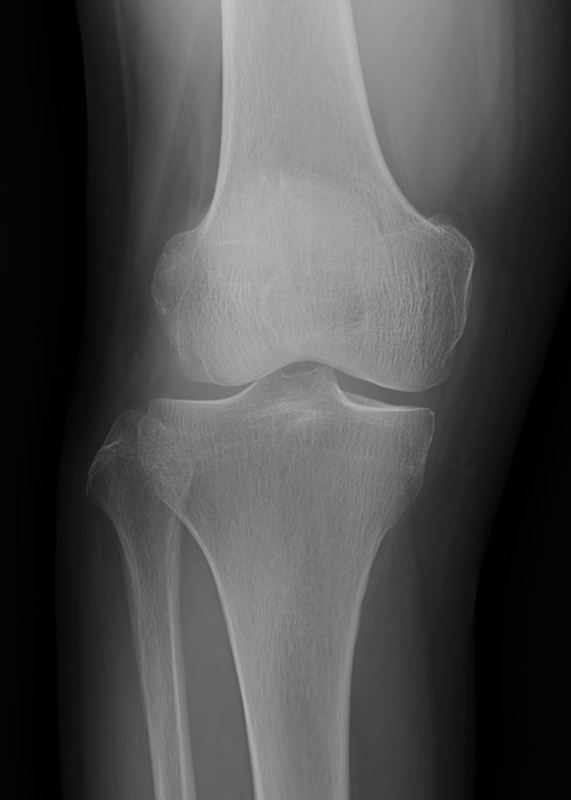

練習を一定期間休むとはれはなくなるが運動量をあげると腫れが出現してしまい試合出場が困難な状態となり治療のため帰国した。XP画像

他院でレントゲンの撮影を行い骨には異常がないと診断され、湿布の処方とヒアルロン酸の治療を5回施行するも効果がなく当院に来院した。XP画像